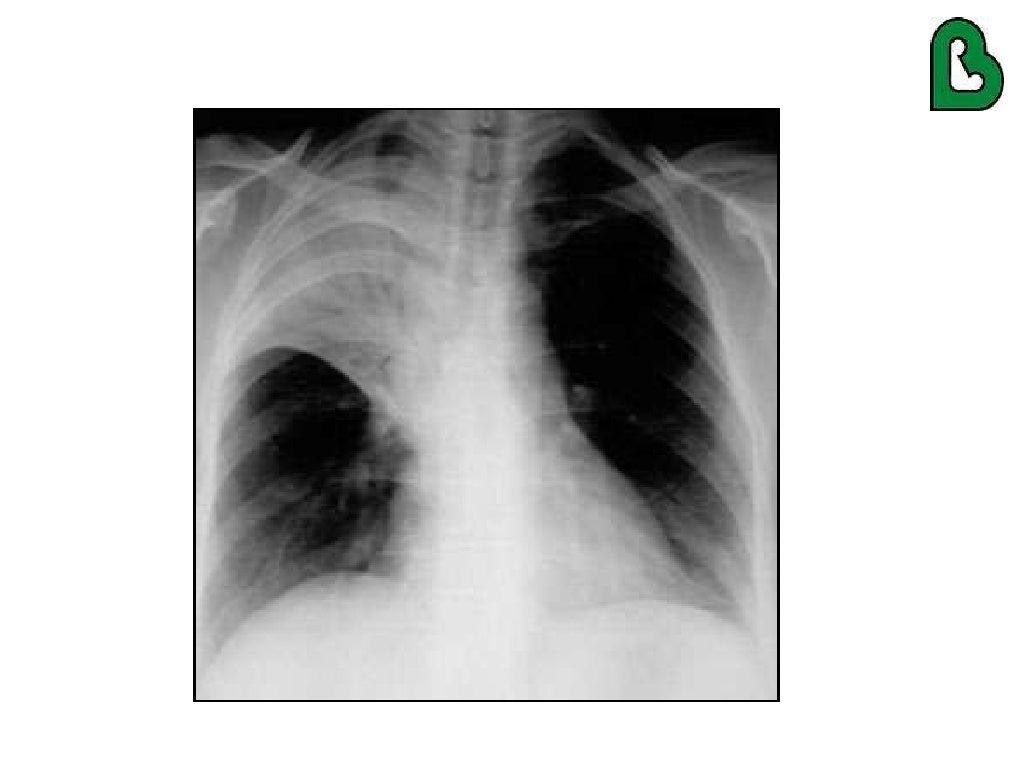

Lung haemorrhage in lupus erythematosus, CT scan Stock Image C044

Lung haemorrhage in lupus erythematosus, CT scan Stock Image C044 Lupus And Your Lungs there are eight types of pleuropulmonary involvement: Find out the signs, risk. Lupus pleuritis, pleural effusion, acute lupus. at some time during the course of their disease, most patients with systemic lupus erythematosus (sle). learn how lupus can affect your lungs and cause inflammation, scarring, or blood clots. learn about the connection between lupus and lung. Lupus And Your Lungs.